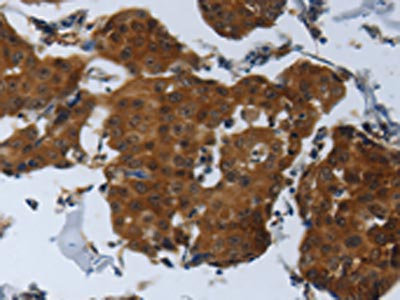

The image on the left is immunohistochemistry of paraffin-embedded Human breast cancer tissue using CSB-PA919263(SPAG4 Antibody) at dilution 1/25, on the right is treated with synthetic peptide. (Original magnification: ×200)

The image on the left is immunohistochemistry of paraffin-embedded Human thyroid cancer tissue using CSB-PA919263(SPAG4 Antibody) at dilution 1/25, on the right is treated with synthetic peptide. (Original magnification: ×200)